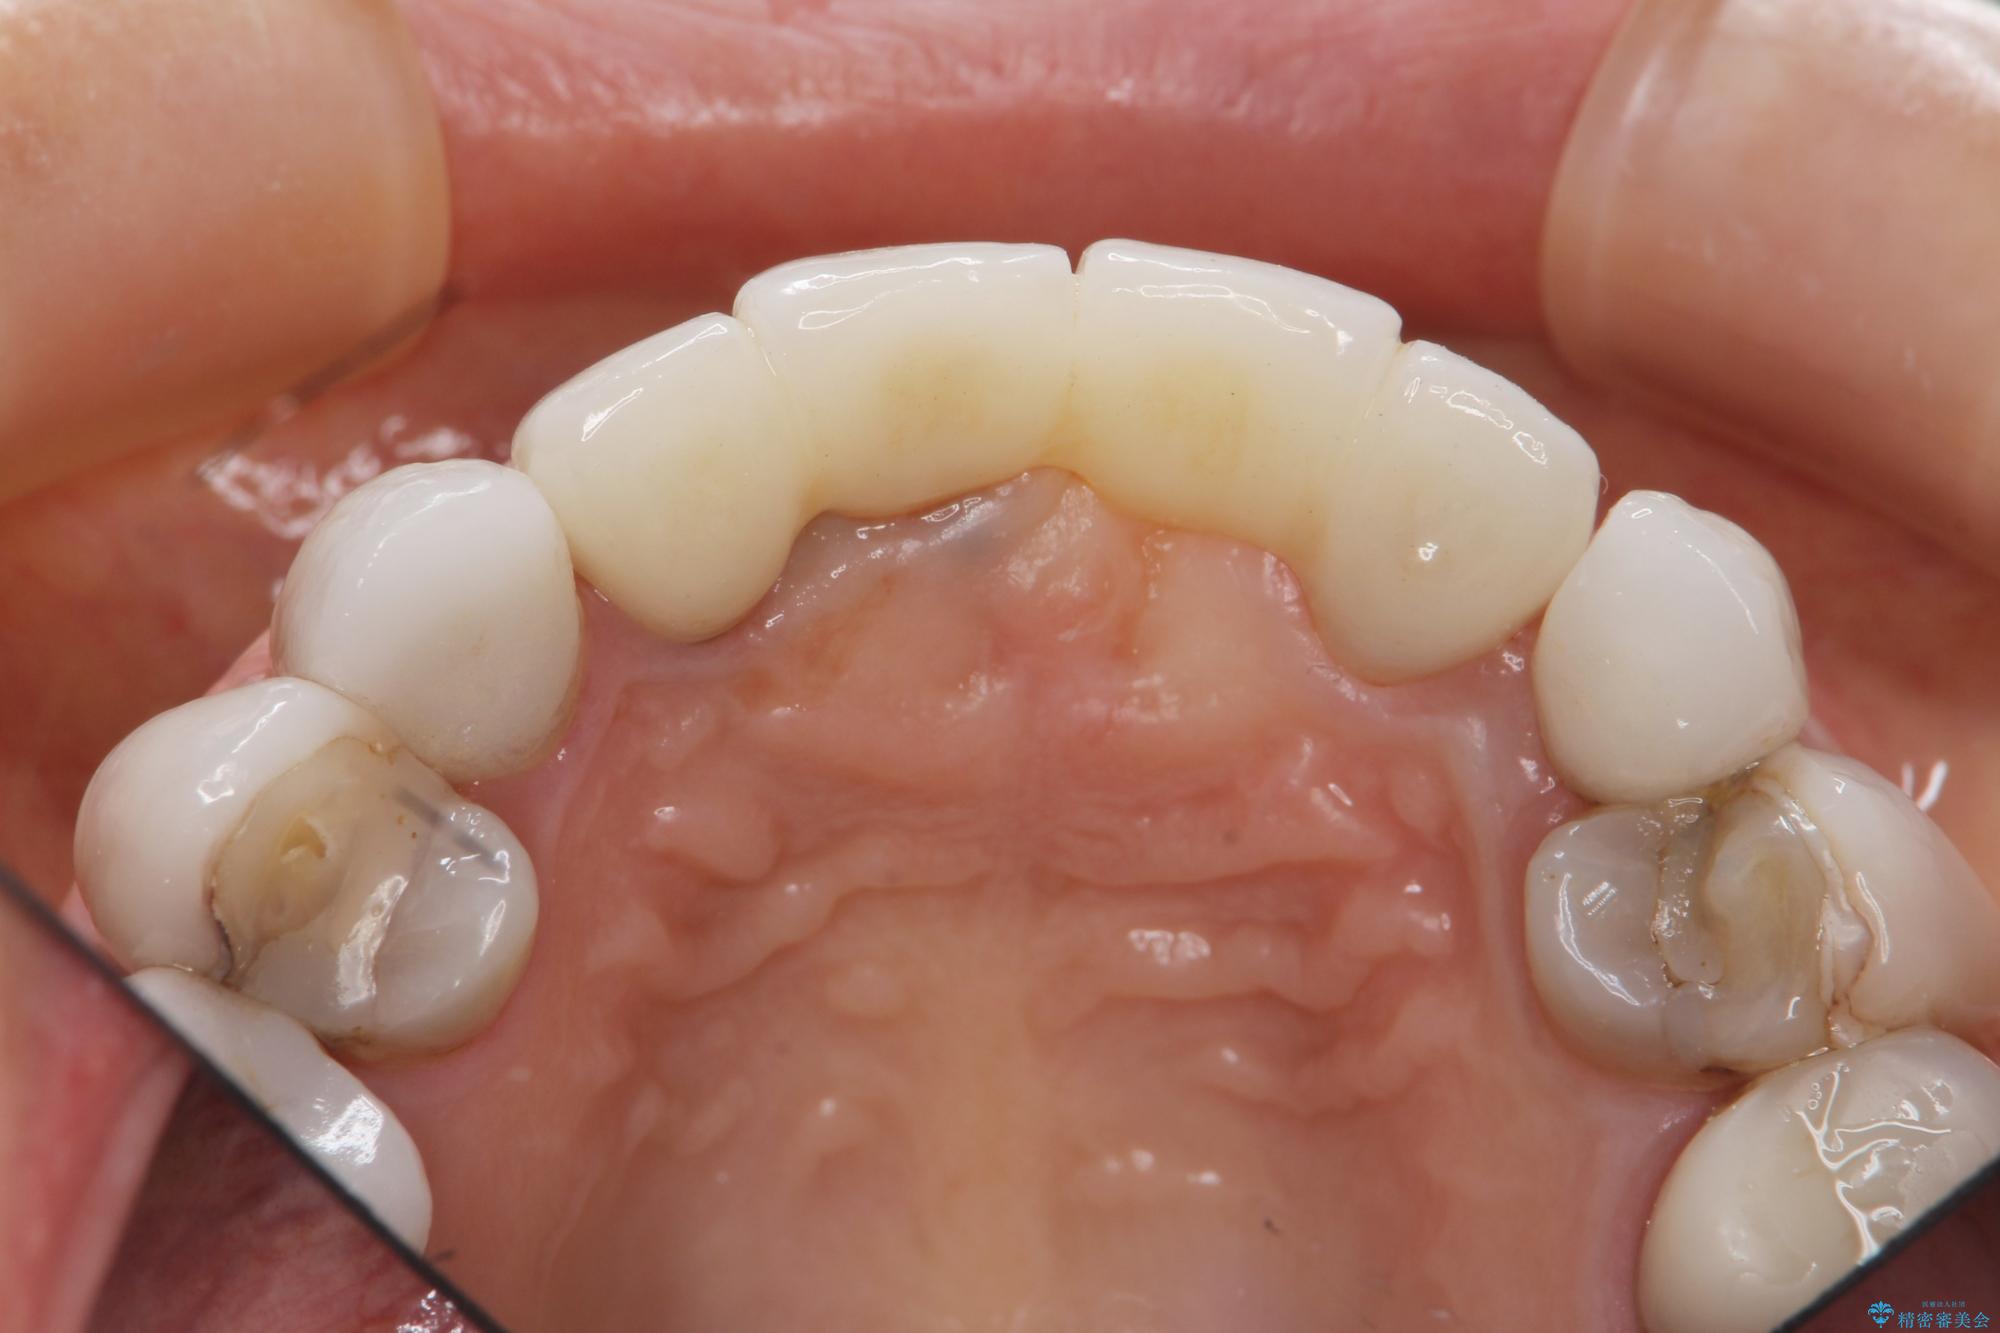

[ セラミック治療 ] 歯ぐきの際の黒ずみを改善したい

- 歯ぐきとセラミックの間の黒ずみが目立つので、きれいに治してほしい。と希望され来院されました。

歯ぐきの位置が変化しクラウン下の歯が見えるようになってしまったことで、審美障害が生じている状態です。

クラウンマージンの再設定を行うことで、黒ずんだ部分を再度覆い、審美障害を改善します。